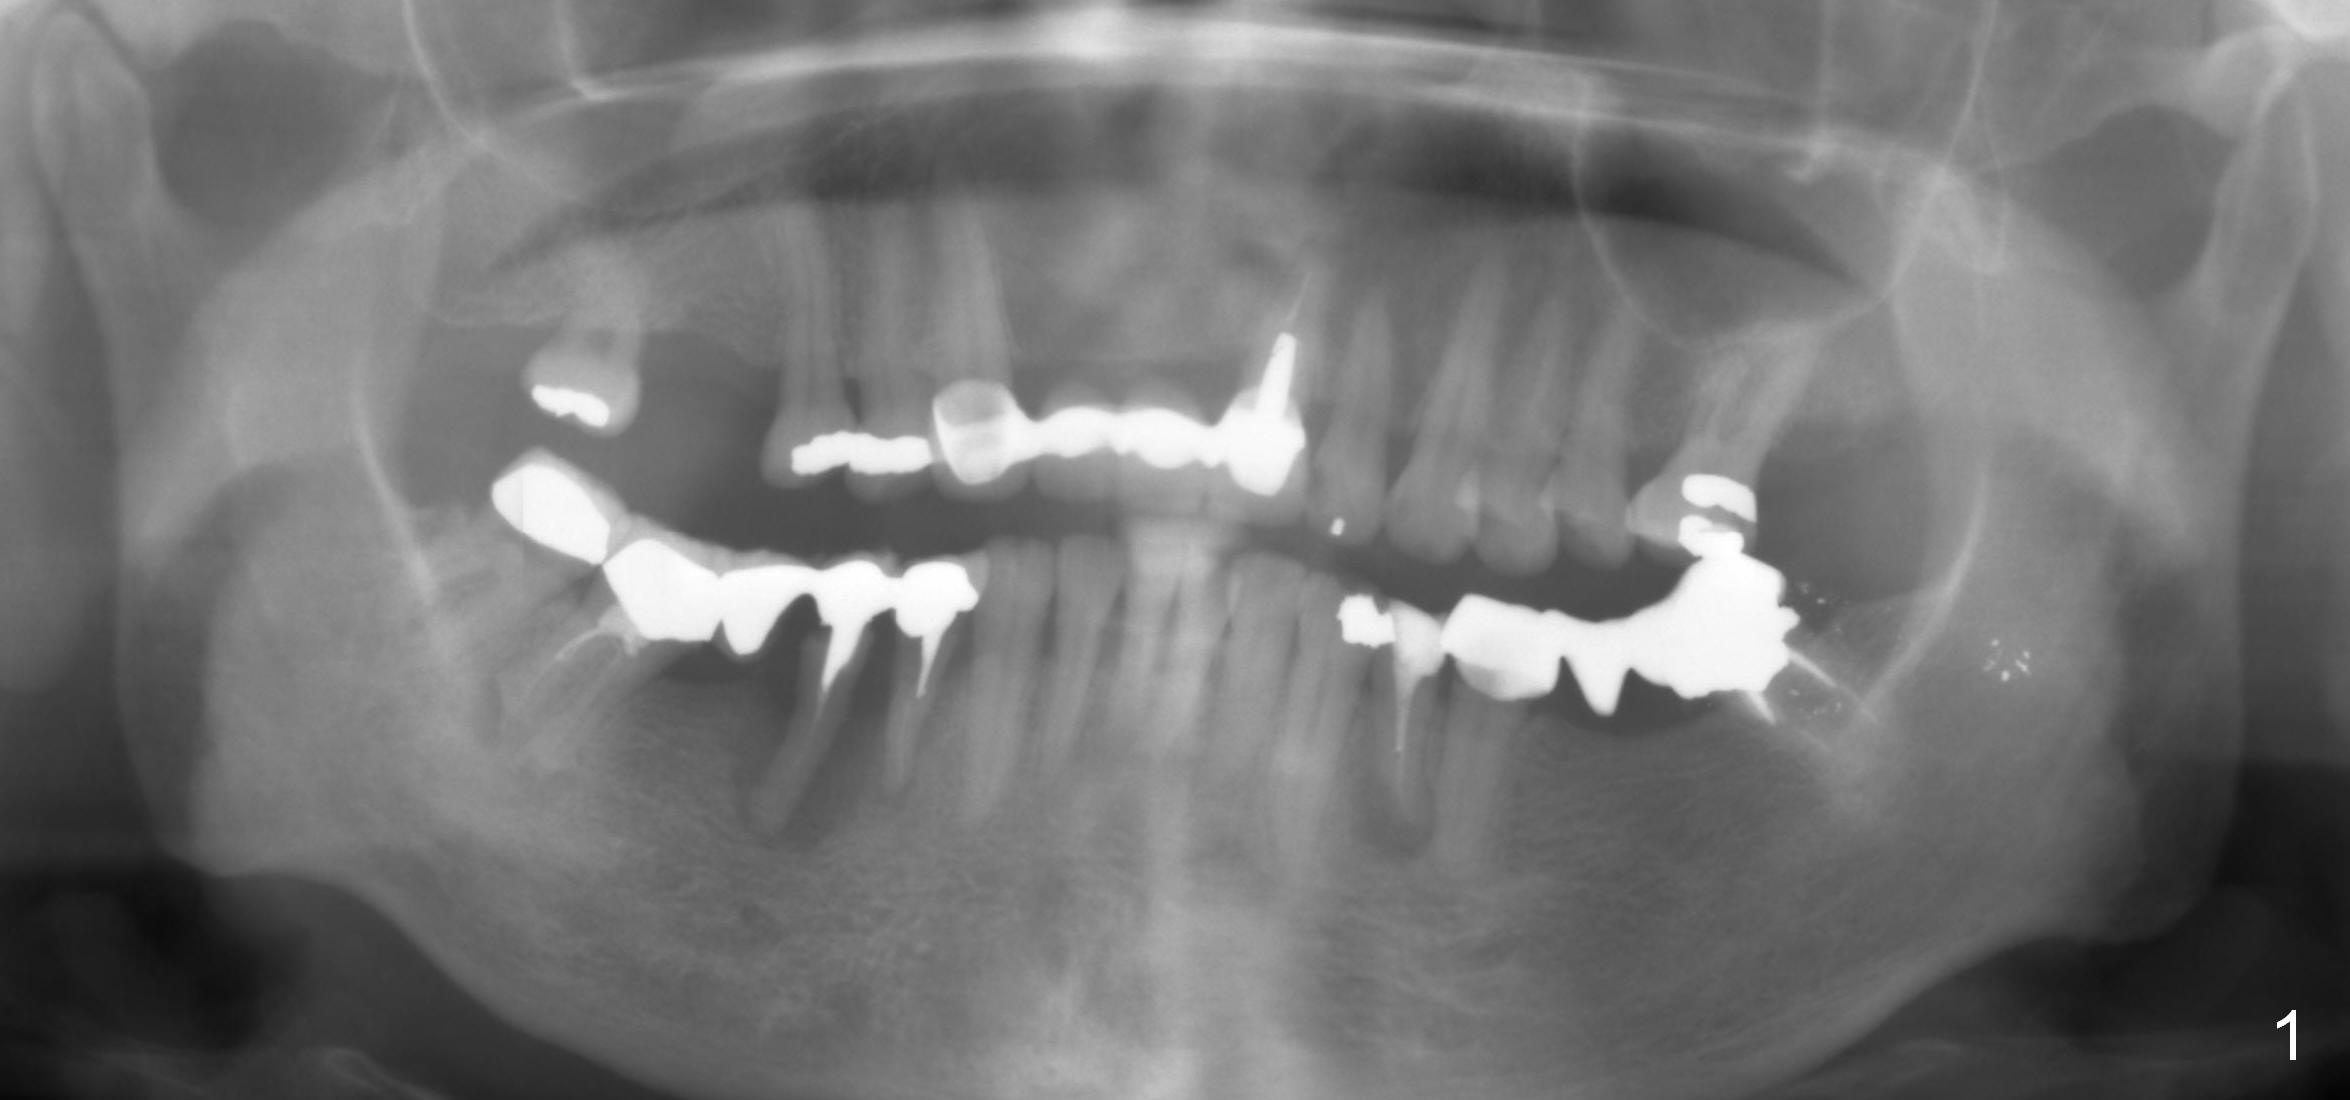

A 50-year-old lady (ZC) has poor dentition (Fig.1). The buccal gingiva of the tooth #29 is erythematous and edematous with deep pockets and severe bone resorption (Fig.2). Two units of the 5-unit bridge is going to be removed (Fig.3). A large implant is to be placed at the site of #29 (socket treated with Metronidazole), while a small one (probably 1-piece) at #30 (narrow mesiodistal space, Fig.4 green outlines). Be care of the mental loop (red dashed line). In fact, the patient wants to have #3 implant placed first.